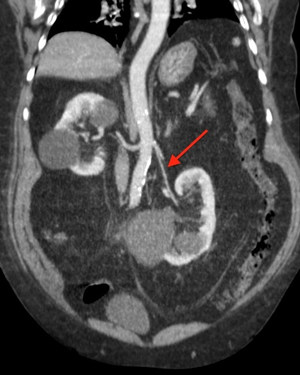

Выявить патологию можно с помощью ультразвукового исследования почек, которое следует проводить как в положении лежа, так и в положении стоя.

Однако результаты УЗИ необходимо подтвердить рентгенологическим исследованием. В процессе диагностики выполняется внутривенная экскреторная урография, при этом делается один снимок в стоячем положении.

Для дифференциальной диагностики подвижности почки используется ультразвуковое цветное доплеровское исследование, позволяющее визуализировать сосуды. При необходимости могут быть применены дополнительные методы, такие как сцинтиграфия и изотопная ренография почек, которые помогают более точно определить наличие опущения почки, если у специалиста остаются сомнения.